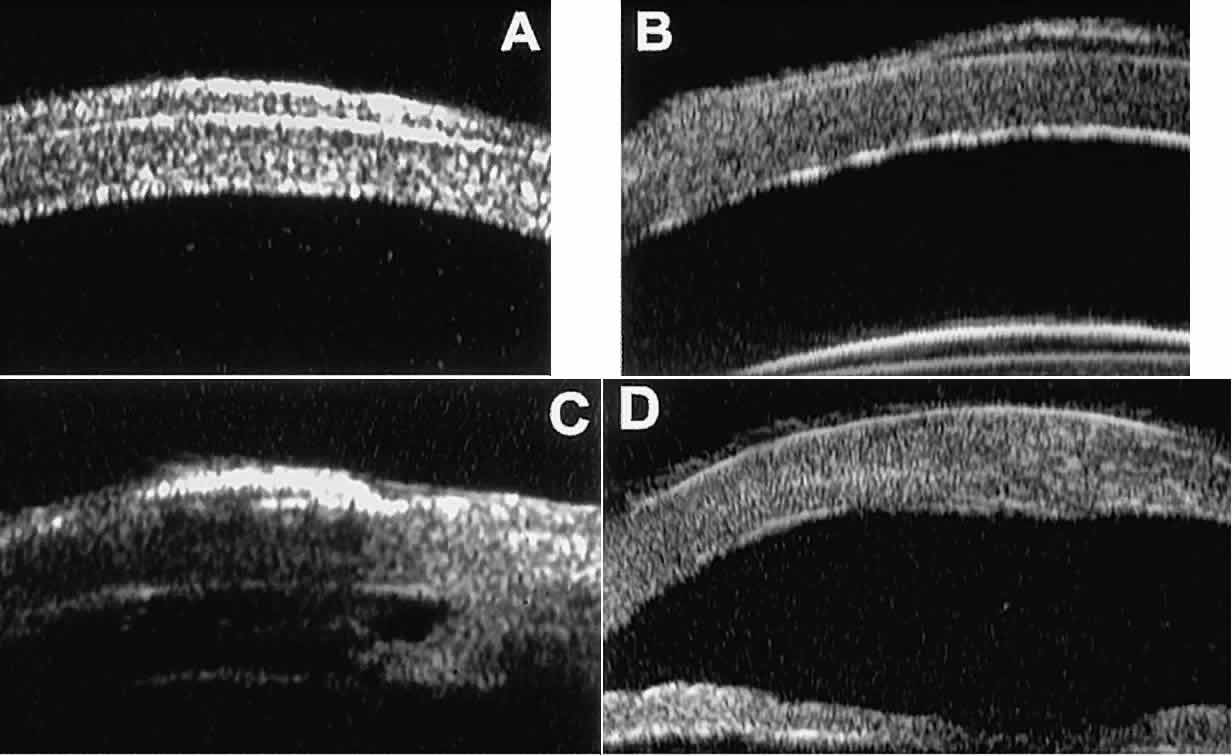

Postoperative UBM imaging of the anatomic changes caused by glaucoma surgery often helps to explain mechanisms of success and failure of the various surgical procedures (Fig. 12).3,4 After laser iridotomy, UBM can show whether the iridotomy is partial thickness (see Fig. 12A) or full thickness (see Fig. 12B) and whether the plane of curvature of the peripheral iris has changed compared with the pretreatment findings. After trabeculectomy (see Fig. 12C), UBM can show whether the scleral aperture is patent or blocked internally, whether the peripheral iridectomy is open or blocked, and whether the filtering bleb is flat, shallow, or deep.9 After tube shunt surgery (see Fig. 12D), UBM can show the position of the tip of the tube and whether its orifice is open or plugged.

Fig. 12. UBM features in glaucomatous eyes after treatment or filtering surgery. A. Incomplete peripheral iridectomy created by laser. B. Full-thickness peripheral iridectomy created by laser. C. Postoperative features of trabeculectomy including peripheral iridectomy, inner scleral defect, thin residual scleral flap, and overlying conjunctival filtering bleb. D. Tube shunt projecting radially into anterior chamber; note that the tube “shadows” deeper structures.

After any type of glaucoma filtering surgery,10 UBM can be used to detect and evaluate the extent of postoperative complications such as ciliochoroidal effusion and cyclodialysis.3,4 In ciliochoroidal effusion (Fig. 13A), UBM shows the ciliary body to be edematous and separated from the sclera by a sonolucent collection of supraciliary fluid. Many ciliochoroidal effusions that are too limited in extent to be detectable by indirect ophthalmoscopy and slit lamp biomicroscopy can be imaged by UBM. In cyclodialysis (see Fig. 13B), UBM shows a well-defined separation between the uveal tissue and the sclera in the region of the scleral spur. The width of the cleft is usually assessed best by means of limbus-concentric images through the region of interest.

Fig. 13. Complications of intraocular surgery. A. Postoperative ciliochoroidal effusion appears as slitlike spaces filled with serous fluid posterior to scleral spur. B. Postoperative cyclodialysis appears as complete separation of iris and ciliary body from sclera in region of scleral spur.